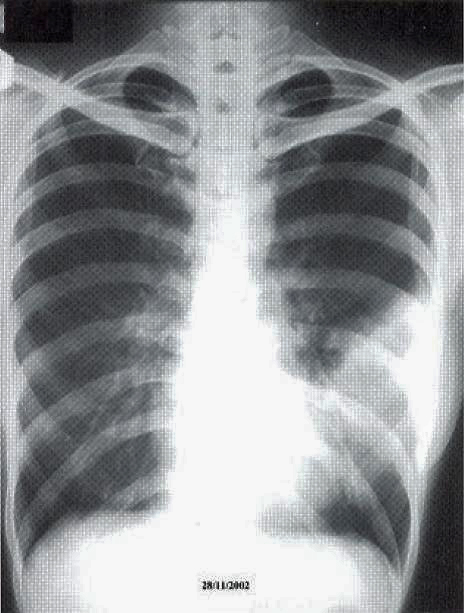

Fig. 1: CXR taken at presentation (a) and 17 days later (b). Left mid zone opacity remained unchanged despite a course of Azithromycin Blood tests revealed normal CBP, ESR & routine biochemistry. Antibodies for HIV 1 & 2 were negative. Thyroid function was normal but thyroid peroxidase antibody was elevated at 81.7 IV/ml (normal <12). CT thorax showed an area of segmental consolidation in the lingular segment of left upper lobe (fig. 2a), with no abnormality detected in other parts of the lungs, mediastinum or body structures. Bronchoscopy revealed nothing abnormal and bronchial washings grew alpha streptococcus but were negative for AFB smear, M tuberculosis DNA or malignant cells. She developed a cough after the bronchoscopy and responded to a course of levofloxacin.

She was treated with chemotherapy – 3-weekly regime of cyclophosphamide, adriamycin, vincristine & prednisolone (CHOP) – and tolerated the treatment well. A CT thorax was performed after 3 cycles of chemotherapy showed a slight reduction in the area of consolidation (fig. 2b).